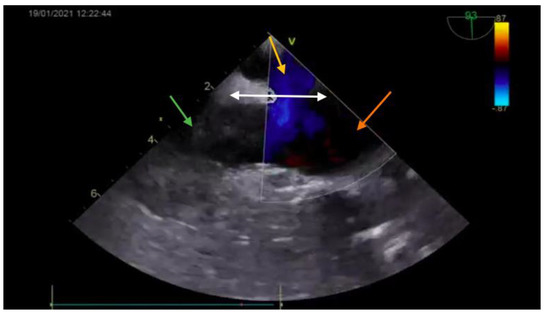

The diagnosis was based on the transthoracic echocardiography (Figure 1 and Figure 2). It revealed an SV-ASD with PAPVD which appeared to open in the right atrium, a dilated right atrium and ventricle, and a left-to-right shunt with Qp:Qs of 2.3 (Qp-pulmonary flow/Qs-systemic flow). The patient had normal pulmonary artery pressure, which was measured during echocardiography.

Postoperative transesophageal echocardiography (Figure 7 and Figure 8) showed the right heart cavities with no dilation and a minimum degree of tricuspid valve functional regurgitation. The inferior vena cava had a 19 mm diameter, and no residual shunts. Also, there was a small accumulation of fluid in the pericardium. The first ECG showed a normal sinus rhythm with 75 bpm, QRS axis at +120 degrees, minor right bundle-branch block with negative T waves in V1, V2. The patient later developed an accelerated junctional rhythm with 50 bpm and narrowed QRS complex, as is characteristic for a minor right bundle-branch block. The pulmonary artery pressure (measured during echocardiography) was normal.

Figure 1. Preoperative echocardiography (bicaval view—Doppler; SVC—green arrow; right atrium—orange arrow; interatrial septum—white arrow) showing the ASD (yellow arrow).